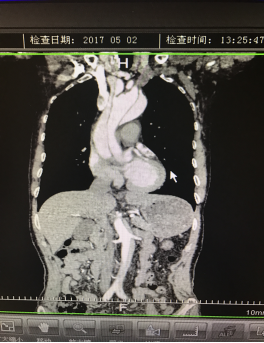

5月2號(hào)劉大伯照常早起干活,突然胸部劇烈疼痛,難以忍受,全身大汗,同時(shí)伴有右上肢發(fā)涼,他心想這次心絞痛比之前嚴(yán)重的多啊,趕緊叫上孩子到吉林國文醫(yī)院心血管內(nèi)科住院,患者長期高血壓病史,血壓一直控制不理想,大夫給他做了檢查,測左上肢血壓:82/45mmHg,右上肢血壓測不出,心率52次/分,右側(cè)肱動(dòng)脈、尺動(dòng)脈、橈動(dòng)脈搏動(dòng)消失,左側(cè)股動(dòng)脈搏動(dòng)較右側(cè)弱。“糟了,雙側(cè)血壓差別這么大,是不是主動(dòng)脈夾層了?”,接診大夫趕緊找來李主任,李主任反復(fù)詢問患者病情,表情突然凝重起來,患者胸痛這么明顯,血壓低的厲害,主動(dòng)脈夾層的可能性很大。二話不說,李主任立即聯(lián)系影像科的醫(yī)生準(zhǔn)備做主動(dòng)脈CTA,移動(dòng)患者做檢查的過程大夫們非常小心,嚴(yán)密監(jiān)測患者血壓變化情況。兩個(gè)小時(shí)后結(jié)果出來了,主動(dòng)脈夾層從升主動(dòng)脈一直撕裂到左側(cè)髂總動(dòng)脈!!

從開始學(xué)醫(yī)到現(xiàn)在已經(jīng)快9年了,主動(dòng)脈夾層患者也見過一些,但像劉大伯這種危險(xiǎn)類型的還是第一次見到,心里真的為他捏把汗,撕裂的主動(dòng)脈隨時(shí)都有可能破裂,生命隨時(shí)可能終止,要知道主動(dòng)脈夾層的死亡率非常的高,約50%的患者發(fā)病后48小時(shí)死亡,約90%的患者發(fā)病1個(gè)月內(nèi)死亡。